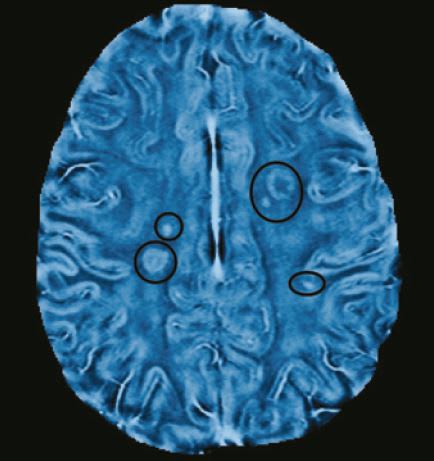

The researchers applied their method to 20 MS patients, who were scanned once a month for six months using both conventional MRI and the new frequency-based method.

Once lesions in the myelin appeared in conventional MRI scans, the scientists went back to earlier frequency-based images of those patients. And, by examining the precise areas of those lesions, they found frequency changes, which indicate tissue damage, at least two months before any sign of damage appeared on conventional scans.